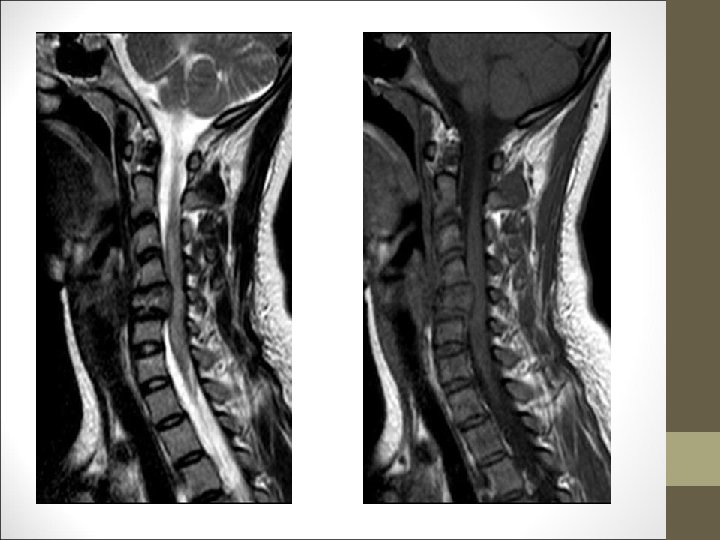

TC Desplazamientos de fragmentos óseos ¿Algo mas? FACULTAD DE MEDICINA DEPARTAMENTO DE CIRUGÍA NEUROCIRUGÍA RM Desplazamientos discales y lesiones ligamentosa